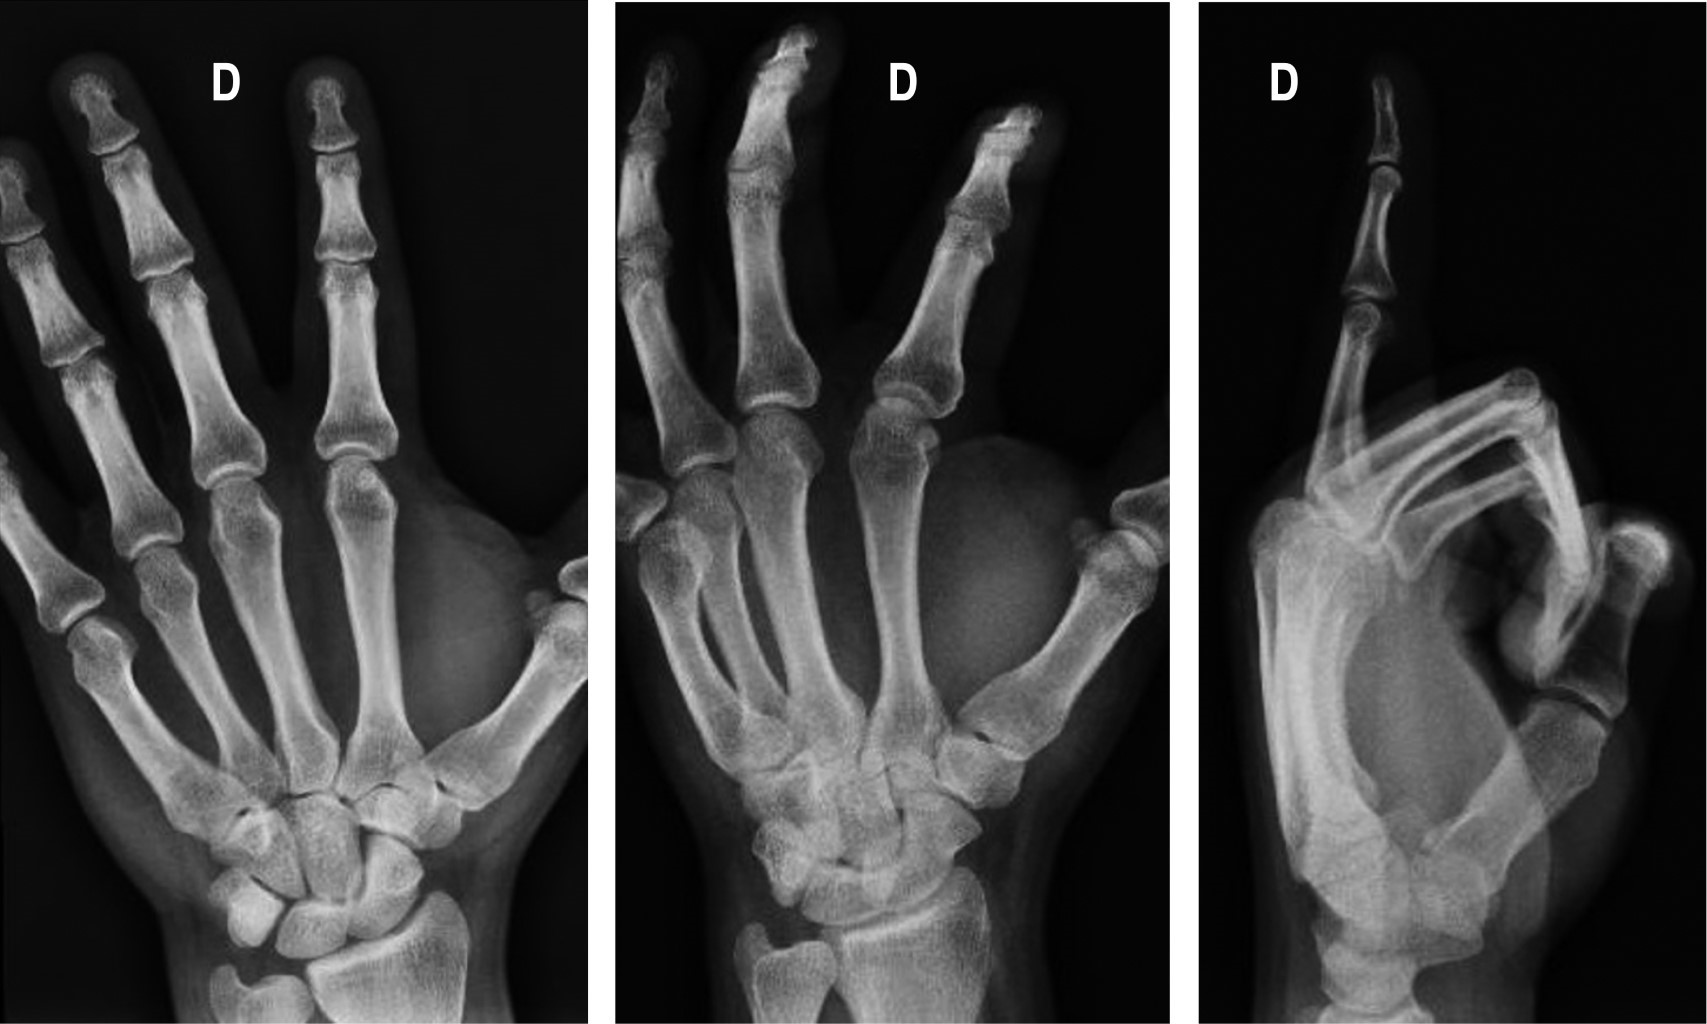

Vascular anomalies are abnormalities that are caused by errors during vascular genesis, which encompass a variety of disorders. They are anomalies that are usually present at birth and may become evident late on in life. Vascular anomalies in the hand, specifically in the fingers, are frequently underdiagnosed; these alterations are confused with congenital malformations in children and a history of trauma or vascular procedures in adults. We present a case of 35-year-old man, with a 1 cm subcutaneous mass in the III extensor zone of the second finger of the right hand, at the proximal interphalangeal joint. The mass that had not caused pain, had been present for three years with no major size changes. Pathology revealed an arteriovenous malformation with no signs of malignancy.

Figure 2